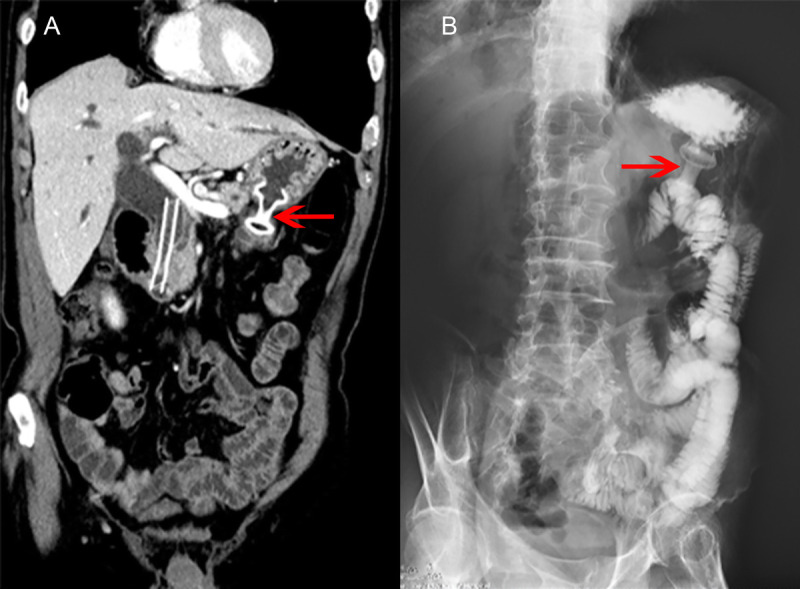

EUS-led breakthrough: An innovative journey to overcome complete gastric outlet obstruction by gastroenterostomy (with video).